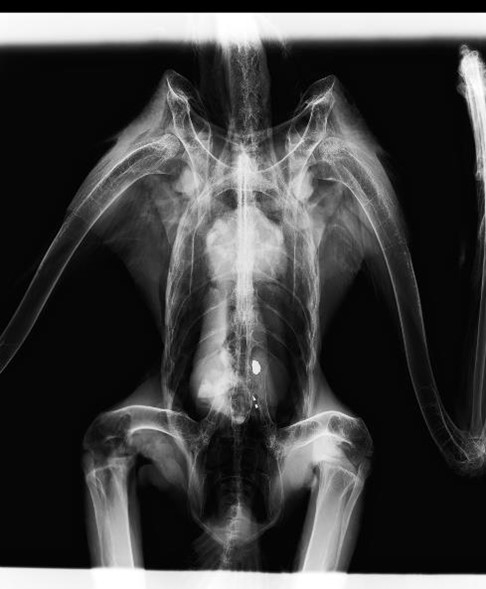

- 胃の中から3個の鉛片を確認。鉛片は、鈍い光沢の金属で、大小不同・扁平であり鉛ライフル弾の破片の可能性が高い。

写真:オオワシのレントゲン写真及び鉛片(猛禽類医学研究所提供)